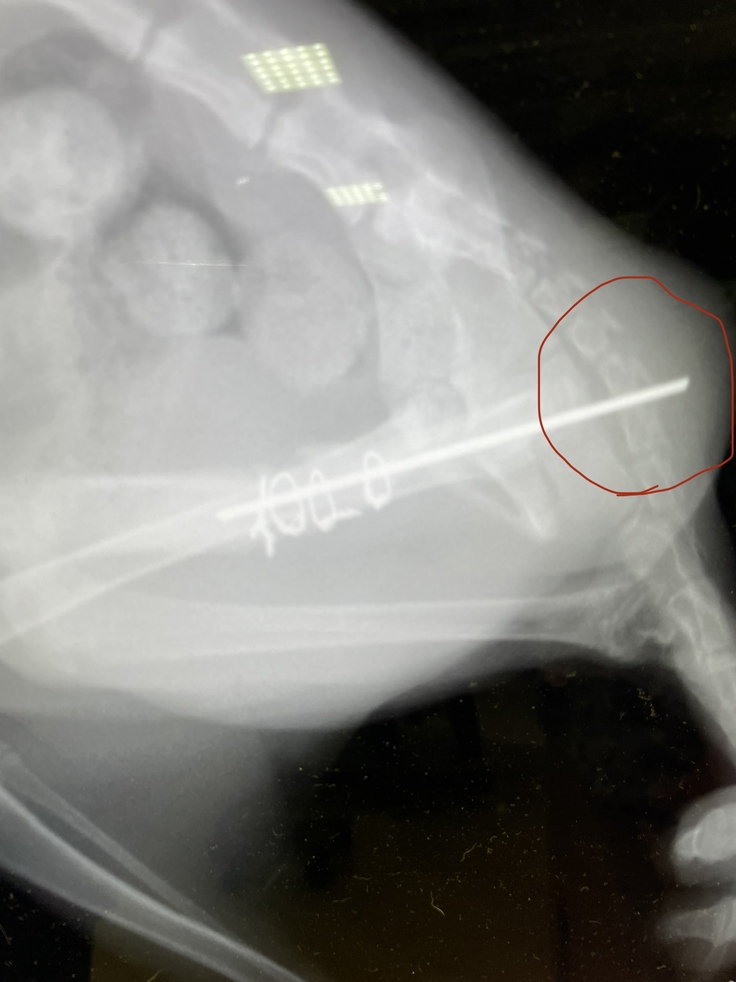

④定期受診(9月11日)

レントゲン撮影を行いました。

骨は綺麗に治ってきています‼︎

しかしピンの位置がズレてきていて、このままでは皮膚を突き破るので、そうなる前にピンを取り除くため、再手術を行うことになりました。本来であればピンを温存する予定でしたが、今の骨の状態であればピンを取り除いても大丈夫とのことでした。

次の受診日の9月16日に再手術を行う予定です。

8月20日に手術をした時には膝関節から大腿骨にかけてピンを入れてましたが、今はピンの位置がズレいて、お尻の皮膚が盛り上がり、突き破りそうになっています。

8月31日と9月11日に撮ったレントゲンを比べても、かなりピンの位置が違います。

↓[8月31日撮影]

↓[9月11日撮影]